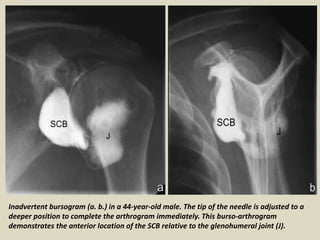

Inadvertent bursogram (a. b.) in a 44-year-old male. The tip of the needle is adjusted to a

deeper position to complete the arthrogram immediately. This burso-arthrogram

demonstrates the anterior location of the SCB relative to the glenohumeral joint (J).